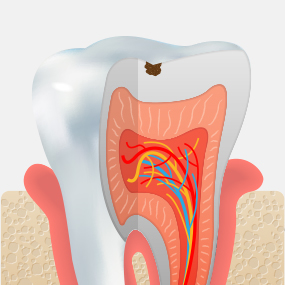

Stages of Dental Caries and Treatment Methods

Enamel Caries

Decay limited to the enamel, the outer layer of the tooth, with little or no pain.

Resin Restoration

Dentin Caries

Decay has progressed into the dentin beneath the enamel, and sensitivity may occur when eating hot or cold foods.

Inlay

Pulpitis

Inflammation has progressed to the dental pulp, causing severe pain that may become difficult to tolerate.

Root Canal Treatment + Crown

Pulp Necrosis

The tissue inside the tooth has become necrotic, and bone around the root is gradually lost due to infection.

Extraction + Implant